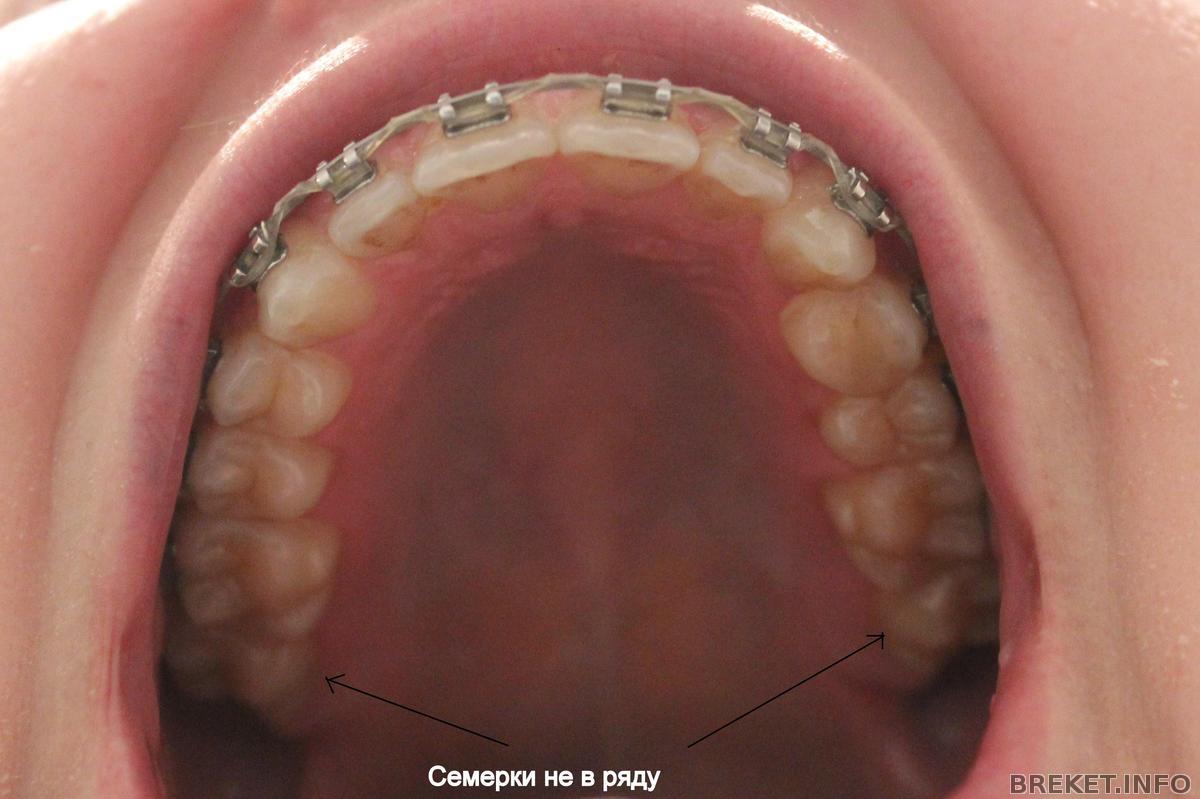

А дело вот в чем. Брекеты мне приклеили начиная от 6ок, т.е. 7 не подключены к системе. Так вот зубы у меня выравниваются, а 7 с ними даже в одном ряду не стоят, как я говорю "пляшут". Мне это очень не нравиться и я очередной раз поинтересовалась у орта, почему 7ки не в ряду с остальными зубами и как это исправлять. Она сказала, что чтобы исправлять это надо клеить брекеты начиная от 7. И мол сейчас это делать накладно, да и не нужно вовсе, потому цитирую "когда мы снимем брекеты, 7ки все равно встанут так как им удобно". Тогда вопрос - а нафига я ношу брекеты, если все потом встанет, как им удобно?!

В общем я настаиваю на том, чтобы мне подключили семерки, она мне объясняет, что в это смысла нет, что они натирают, что на них внимание вообще не обращают, что при улыбке у меня их не видно, что потом они все равно встанут на свое место и т.д.

Еще у меня завалены 6ки на нижней челюсти, на что она тоже не обращает внимание. Короче, вопрос, у кого как с этим делом обстоят дела???